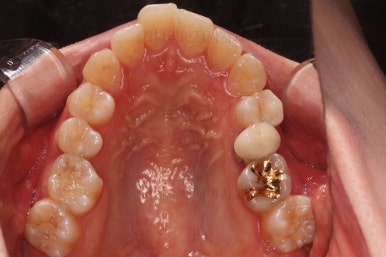

3. 치료경과

악궁확장을 먼저 시행합니다.

아랫니에 비해서 윗니의 악궁의 폭이 좁기 때문에 가로폭을 먼저 개선합니다.

이번 환자분은 성인이긴 했지만 미니스크류 없는 일반 타입의 악궁확장장치로 시도하기로 했습니다.

악궁확장 이후, 유지단계 동안 확장의 유지에 필요한 치아를 제외하고는 브라켓을 부착하게 됩니다.

이번 환자분이 선택한 장치는 엠파워 클리어라고 하는 자가결찰 세라믹 장치인데요.